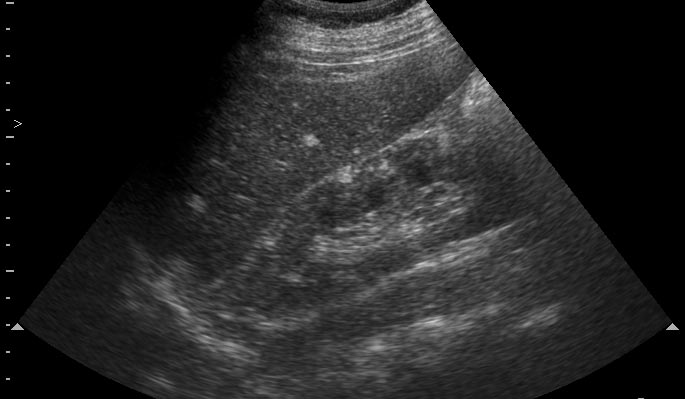

Парень 16 лет с эпилепсией. Изменения почек симметричные с обеих сторон. Ваши рекомендации?

УЗи почек - туберoзный склероз (болезнь Бурневиля)

В паренхиме поллиморфные гиперэхогеные очаги по типу ангиолипоматоза.Учитывая двустороннее поражение,да еще умственную отсталость,то возможна врожденная патология,которую Марио уже назвал( я бы остановилась просто на ангиолипоматозе

)

Все верно, туберoзный склероз. На сонограммах определяются образования типа ангиомиолипом/гемангиом почек/печени. Наличие судорог редполагает сходные изменения головного мозга - доказано на КТ.